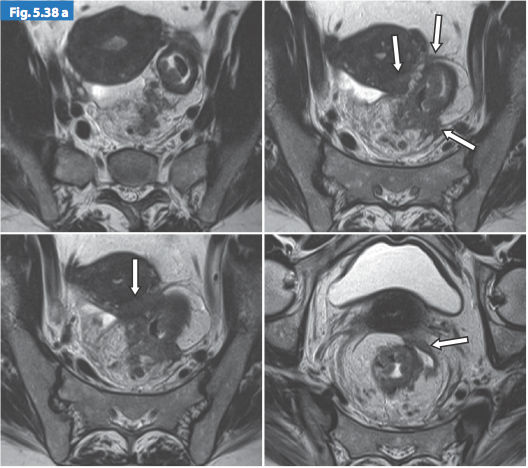

Hình 4. Khối ung thư trực tràng xâm lấn mỡ mạc treo trực tràng

Hình 5. Khối ung thư trực tràng giai đoạn T3 MRF-